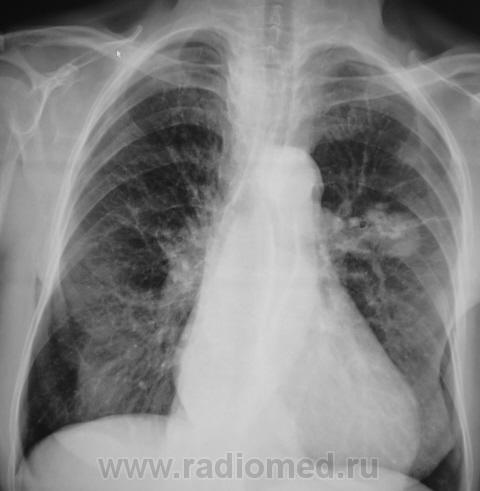

А клиника какова? ПО снимкам можно предположить и новообразование (как мне кажется наиболее вероятно) и туберкулому S6

Помоему образование, тяжистость ну очень интересная.

Неоднородность, очень плотное... гамартрохондрома, тератома, а-v-аневризма... Мне недостаточно для диагностики

Здравствуйте, уважаемый Валентин Львович! Склоняюсь к мысли периферического новообразования. На томограммах хорошо виден патогномоничный симптом "тень на веревочке". Ну и остальное. Неровные, нечеткие контуры, неоднородная структура. Зло!

Ну, мы так и сделали, выставили "периферический". Пациент уже в областном ОД.

В ООД был прооперирован, но дальнейшей судьбы не знаю.